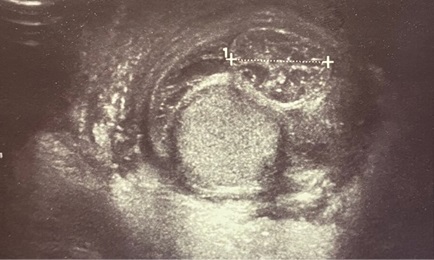

Характерными ультразвуковыми симптомами явились (см. рис. 1):

- гематома позади яичка при сохранении/нарушении целостности его белочной оболочки;

- неоднородность структуры придатка при малом сроке травмы, исключающем развитие посттравматического эпидидимита;

- явное нарушение контура придатка.

Рис. 1. Б. Придаток в поперечном срезе — отёчен, неоднородной структуры